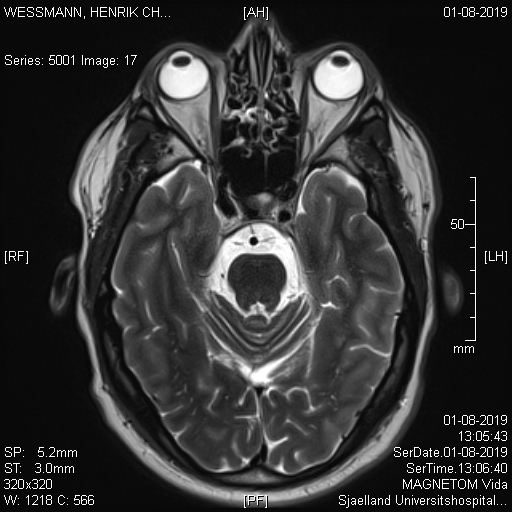

Jeg henvendte mig på Roskilde Sygehus for at få billederne fra min MR scanning og det er til at grine og græde over..